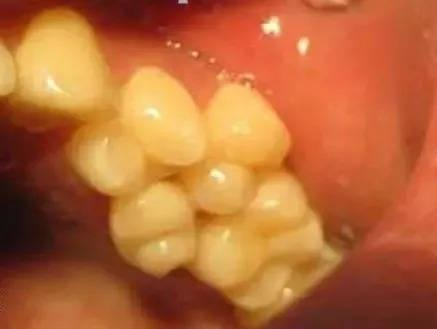

多生牙又称额外牙,是正常牙列以外的多余牙齿,是多于正常牙数以外的发育异常的牙齿。在形态上,其多为锥形牙或者过小牙,也可与正常牙齿形态相似。在数量上,可分为单发或者多发。在位置上,可分为正中、前磨牙区、磨牙区等,其中上颌前牙区最为常见。在空间上,可萌出在口腔,一般口内检查可见;也可埋伏阻生,只能通过X线检查发现。

多生牙往往没有临床症状,多在拍片时偶然发现。但其危害不容忽视,可影响恒牙的发育,可引起恒牙的迟萌或者阻生,恒牙牙根形态发育异常,出现牙间隙、牙齿扭转或者移位。多生牙可能横着、倒着、斜着埋伏在颌骨里占据正常牙齿的位置,从而影响恒牙的萌出。甚至,久而久之,多生牙阻挡恒牙牙根正常生长方向,导致恒牙牙根弯曲。此外,多生牙也可以在乳牙脱落前后萌出,临床上我们看见形态不正常的牙齿或者牙尖。萌出的多生牙占据了正常恒牙在牙列中的位置,造成牙列不齐。

1 牙列拥挤

2 牙齿移位

3 牙间隙大

4 恒牙牙根发育异常